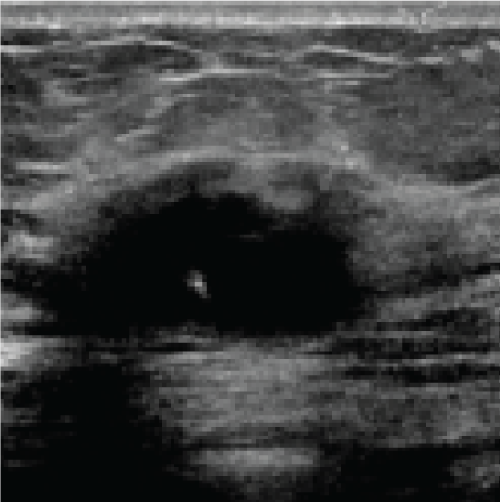

In the sequence of processing ultrasound images, Fig. 20 shows the original input image acquired from an ultrasound scan from the dataset provided in [41]. This image is subsequently resized for standardization, as illustrated in Fig. 21, to maintain consistency throughout all following processing processes. Next, Fig. 22 shows the filtered version of the picture, which has been filtered bilaterally to minimize noise while keeping critical edge details required for accurate anatomical structure detection. Fig. 23 shows further picture enhancement using the Non-Local Means (NLMS) filter, a method chosen precisely for its ability to preserve detailed details while increasing contrast. Finally, Fig. 24 shows the contour of the tumor, which clearly defines the afflicted area and serves as an input for feature extraction and subsequent classification stages.

Figure 20: Original image (Ultrasound Scan)

Figure 21: Resized image

Figure 22: Filtered image

Figure 23: Enhanced image via NLMS filter

Figure 24: Contour of tumor